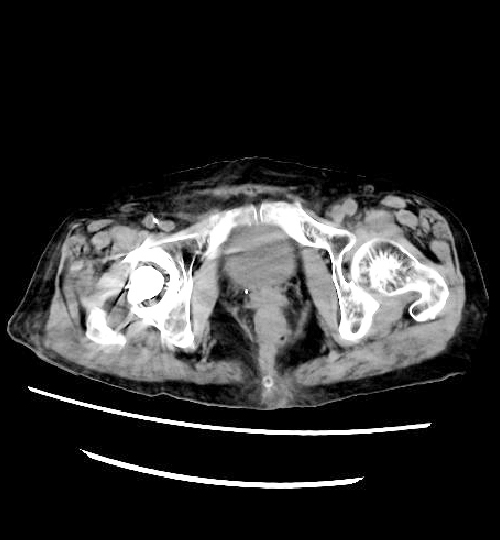

なお、従来の装置より実施しておりますCTCと称される短時間で苦痛の少ない大腸のCT検査も、変わらず対応しております。こちらも、より被ばく線量を低減した撮影ができるようになっております。